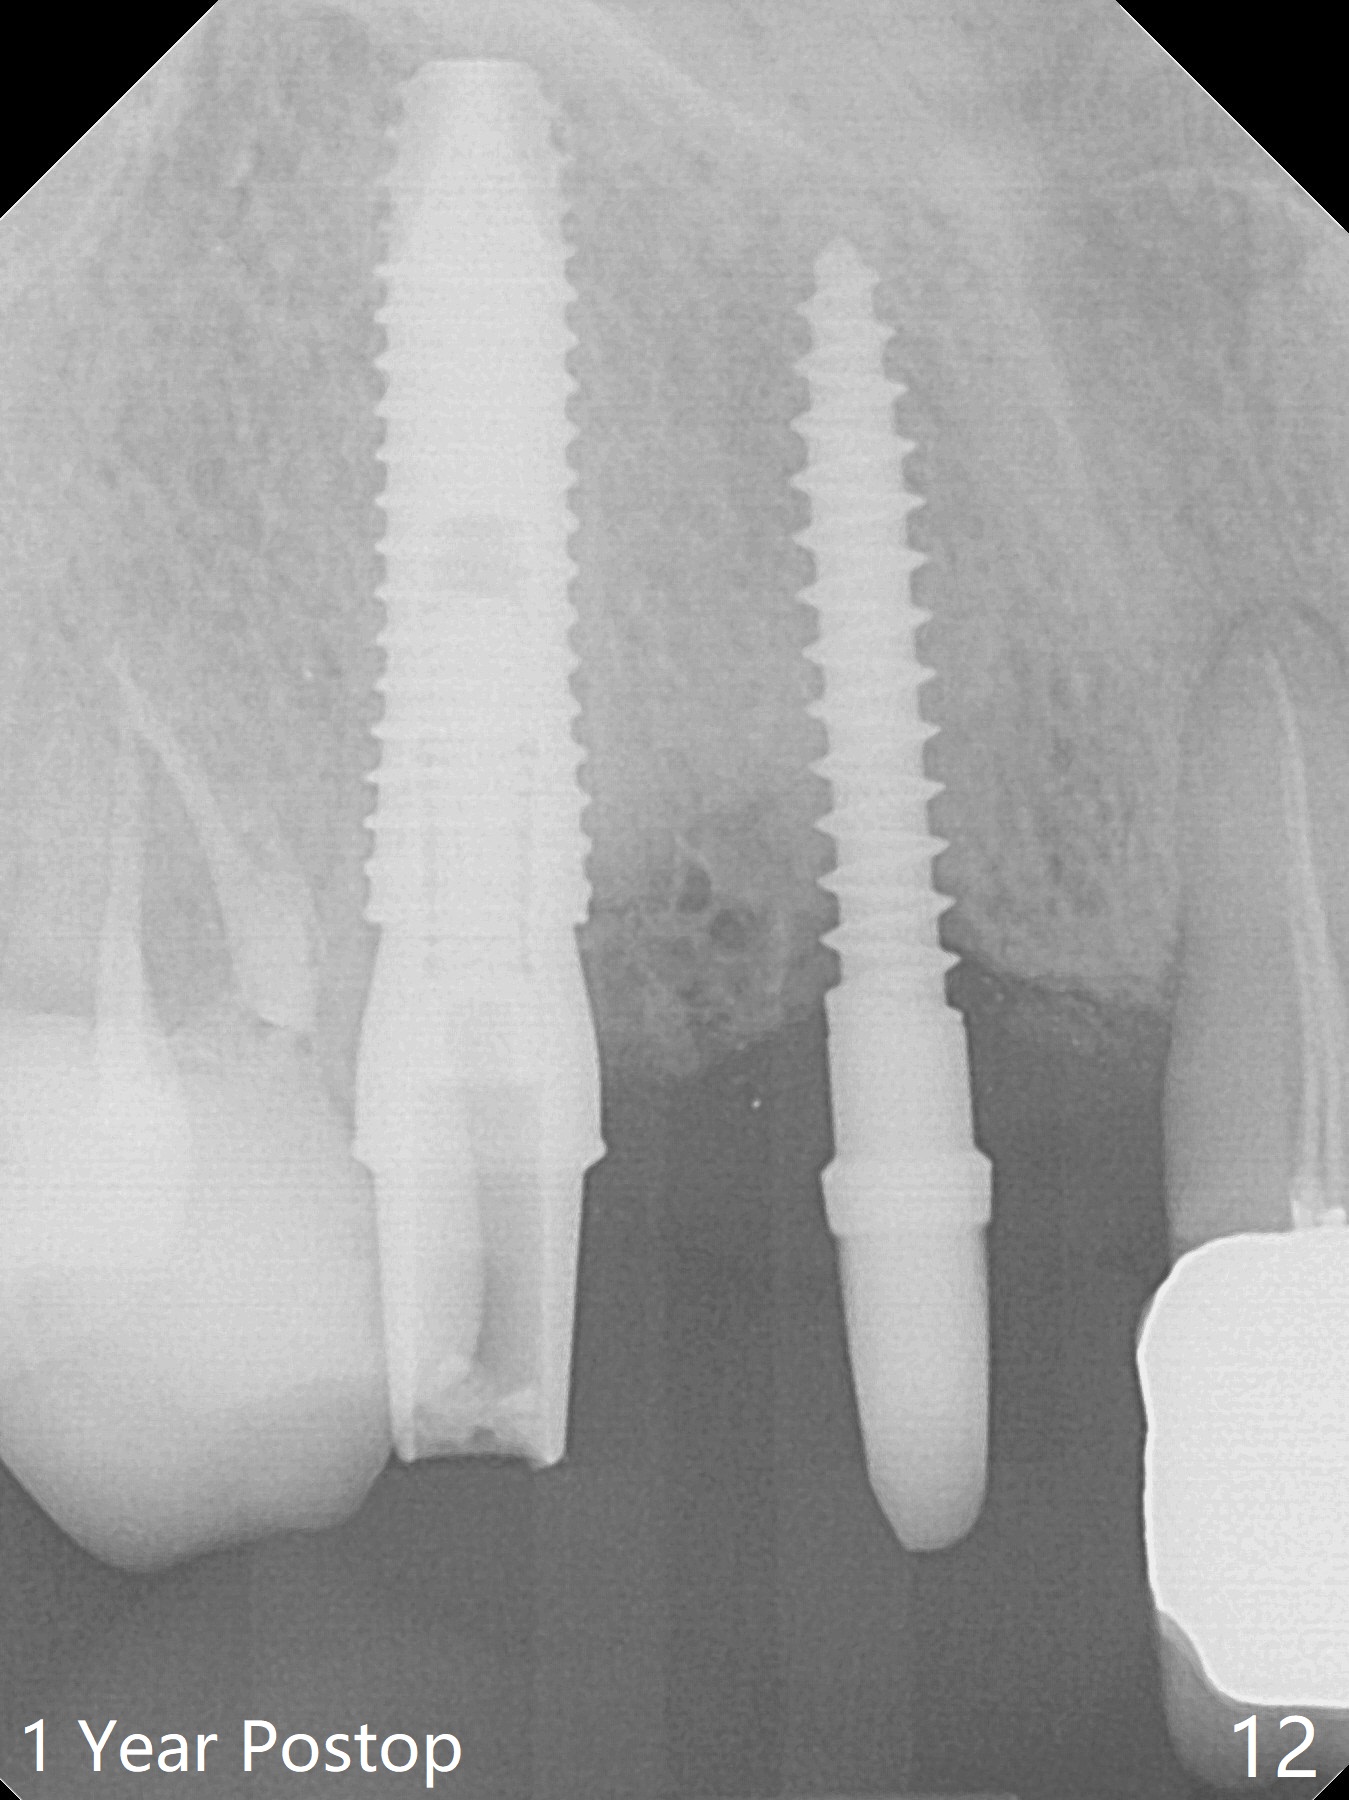

Since the ridge at #7 is ~ 4 mm, a 2.5x14 mm 1-piece implant is placed (Fig.8) after 1.2 mm (Fig.7), and 1.5 mm drills at 12 mm and 2 mm drill at 8 mm. Later the implant is placed deeper (Fig.10). There is no bone loss 7 or 12 months postop, respectively (Fig.11,12). After Diode gingivectomy, there is papillary formation (Fig.13). No provisional is provided after impression (with the abutment torqued at #6) for oral hygiene. With access holes at #6 and 7, crowns are bonded with minimal residual cement (Fig.14 <, which is removed later). There is no hard (Fig.15,16) or soft (Fig.17 *) atrophy 26 months postop, i.e., 13 months post cementation, due to the presence of socket shield (Fig.15 <, as compared to Fig.1). In fact the tooth #8 has mobility and fremitus (short root/poor crown/root ratio, Fig.16); occlusal adjustment is done 13 months post cementation. The crown is dislodged 2 years 1 month post cementation; a prefabricated post is being tried in (Fig.18). There is no atrophy, bone loss or infection at #6 (with socket sheath (*)) or 7 two years 5 months post cementation (Fig.20-27).